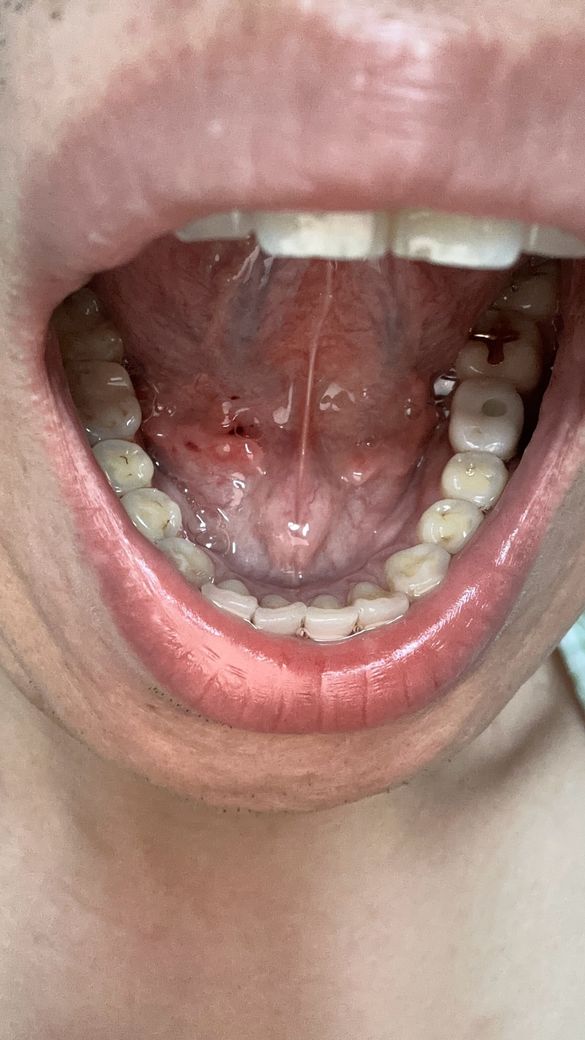

양치하다가 칫솔로 눌렀는데 아파지고 빨개진거같아요

빨갛게 된부분이 있는것같고 그래서 이거 병원가봐야되는지 그냥 냅둬도 괜찮음지 궁금해요 어떻게하는게 좋을까요?? 병원은 무슨과인가요?

• 4번 째 사진

일시적으로 상처가 생긴거나 최대한 자극만 가지 않도록 하면 시간이 지나면 괜찮아 지실꺼에요.

구강 내 점막 조직이 양치질을 하다. 자극을 받게 되면 불편감이 있을 수 있습니다. 이런 불편감은 대부분 시간이 지나면서 해당 부위를 자극하지 않으면 줄어들게 됩니다.